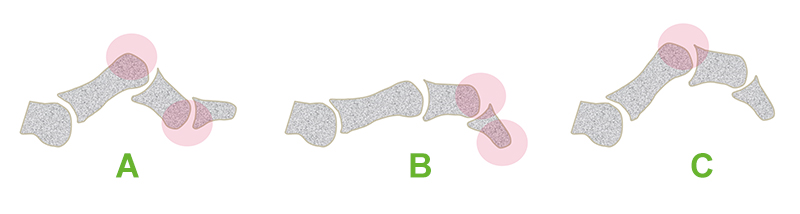

Die Flexionsfehlstellungen der Kleinzehen, welche in flexible und kontrakte Deformitäten unterschieden werden, bedürfen je nach Lokalisation der Beugefehlstellung einer klaren Begriffstrennung (Hepp 2004). Bei der Hammerzehe kommt es zu einer maximalen Beugung im Zehenmittelgelenk und einer Überstreckung im Grundgelenk (Abb. 3a), bei der Malletzehe dagegen zu einer alleinigen, maximalen Beugung im Endglied (Abb. 3b) Die Krallenzehe entsteht oft aus einer Hammerzehe. Es findet sich eine Dorsalextension im Grundgelenk und eine Beugefehlstellung sowohl im Mittel- als auch im Endgelenk, wobei die die Zehenspitze den Boden in der Regel nicht mehr berührt (Abb. 3c). Die in den Abbildungen verdickt gekennzeichneten Hautareale sind bei den einzelnen Deformitäten vermehrt druckbelastet und damit beim DFS ulcusgefährdet. Da die Begriffsbestimmungen häufig in der Literatur unklar sind und mehrdeutig verwendet werden empfiehlt sich oft die Beschreibung der genauen Deformität, z.B. Hyperextension im Metatarsophalangeal-Gelenk (MTP), kontrakte Flexionsfehlstellung im proximalen Interphalangealgelenk (PIP) oder distalen Interphalangealgelenk (DIP).